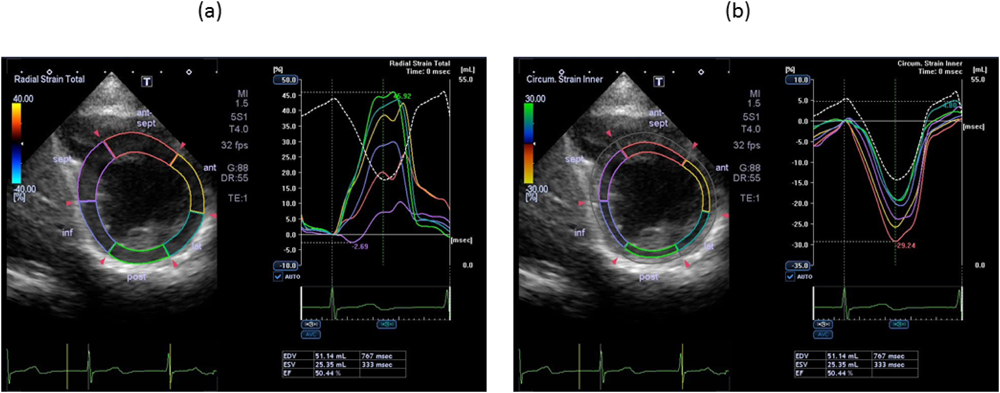

Pediatric Cardiology and Cardiac Surgery 32(2): 78-86 (2016)

Fig. 3 Examples of strain curves

(a) Radial strain and (b) circumferential strain in the patient following an arterial switch operation for transposition of the great arteries.